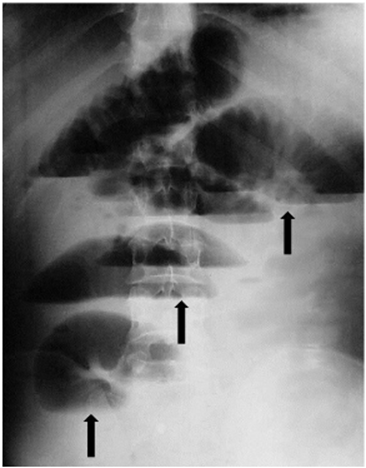

Se trata de un hombre de 46 años de edad, sin antecedentes de intervención quirúrgica, quién acudió al servicio de urgencias por presentar dolor abdominal tipo cólico, náuseas, vómito bilioso frecuente y ausencia de flatos y deposición. A la exploración física se encontró mucosas secas, abdomen distendido, ruidos hidroaéreos aumentados, hipersonoridad difusa a la percusión y ampolla rectal vacía al tacto rectal. La radiografía simple de abdomen en bipedestación, mostró la presencia de niveles hidroaéreos centrales en escalera y distensión de asas yeyunales e ileales (Figura 1).